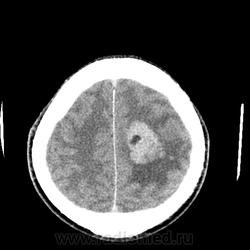

Мужчина 66 лет. Поступил с подозрением на ОНМК. Жалобы на атаксию и когнитивные нарушения (родственники рассказали о его плохой памяти, рассеянности, забывчивости, в последнее время, а также о нарушении речи и невнятности в произношении "мямлил"). Объемное образование в теменной, височной доли и базальных ядрах слева. Вазогенный отек. Выраженный масс-эффект. Латеральная дислокация вправо на 1,5см. Не могу дифференцировать интравентрикулярно ли, субэпендимарно ли расположено или за счет такого масс-эффекта? Ипсилатеральный желудочек компремирован, контрлатеральный компенсаторно расширен, височные рога боковых желудочков расширены, III желудочек значительно сужен и не дифференцируется, IVинтактен. Сильвиев водопровод сужен, достоверно не дифференцируется, супраселлярная цистерна сужена. Субарахноидальные борозды и конвекситальные пространства сужены. Выраженно диффузно очень интенсивно накапливает КВ. DDs: более вероятно: менингиома,  менее вероятно: субэпендимарная АСЦ, анапластическая АСЦ, глиобластома. Сложилось впечатление с большей вероятностью о внутрижелудочковой менингиоме с экстравентрикулярным ростом.

Я и написал: "Не могу дифференцировать интравентрикулярно ли, субэпендимарно ли расположено или за счет такого масс-эффекта?" Сам однозначно не уверен, то ли внутри, то ли такая дислокация. Хотя такое впечатление, что опухоль как раз таки растет из сосудистого сплетения заднего рога левого желудочка.

А так видно, что опухоль растет изнутри расширяя желудочек.

Она растет из сосудистого сплетения заднего рога левого бокового желудочка, поэтому его расширяет, а вот передний рог как раз компремирует